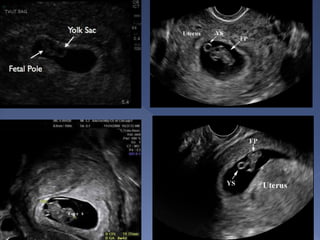

 Earliest sign of

pregnancy

 seen at 4-4.5 weeks

 It is intradecidual

 Surrounded by

decidual reaction

 Can be used for

dating.

 A normal gestational

sac grows by 1 mm

per day.

 presence of a yolk sac : seen at

approximately 5.5 weeks or with a beta-

HCG of ~7000m IU/ml

 presence of the double decidual sign

 Seen at 5 weeks

gestation

 Differentiates

true from pseudo

gestational sac

 Seen at 20 mm

sac diameter

abdominally and

8 mm sac

diameter

vaginally

 Seen at 6

weeks vaginally

 Should be seen

at sac diameter

of 18mm

vaginally and

25mm

abdominally

 Heart beat is

seen at CRL of

5mm vaginally

 Gestational sac – 4 to 5 weeks

 Yolk sac – 5 to 6 weeks

 Fetal pole - 6 to 7 weeks

 Cardiac Activity - 6 to 7 weeks.